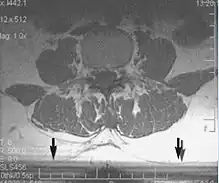

Metal artifacts

Metal artifacts occur at interfaces of tissues with different magnetic susceptibilities, which cause local magnetic fields to distort the external magnetic field. This distortion changes the precession frequency in the tissue leading to spatial mismapping of information. The degree of distortion depends on the type of metal (stainless steel having a greater distorting effect than titanium alloy), the type of interface (most striking effect at soft tissue-metal interfaces), pulse sequence and imaging parameters. Metal artifacts are caused by external ferromagnetics such as cobalt containing make-up, internal ferromagnetics such as surgical clips, spinal hardware and other orthopaedic devices, and in some cases, metallic objects swallowed by people with pica.[3] Manifestation of these artifacts is variable, including total signal loss, peripheral high signal and image distortion (Figs 3 and 4).[1] Reduction of these artifacts can be attempted by orientating the long axis of an implant or device parallel to the long axis of the external magnetic field, possible with mobile extremity imaging and an open magnet. Further methods used are choosing the appropriate frequency encoding direction, since metal artifacts are most pronounced in this direction, using smaller voxel sizes, fast imaging sequences, increased readout bandwidth and avoiding gradient-echo imaging when metal is present. A technique called MARS (metal artifact reduction sequence) applies an additional gradient, along the slice select gradient at the time the frequency encoding gradient is applied.